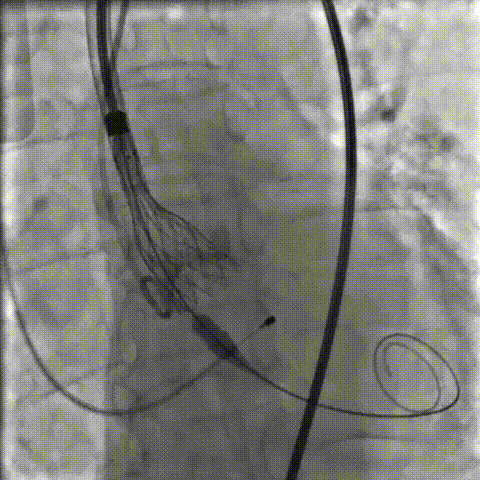

手术影像记录

主动脉根部造影

18mm球囊预扩

AV26瓣膜工作位造影

缓慢脱钩

23mm球囊后扩

后扩后造影:无漏

术中剪影